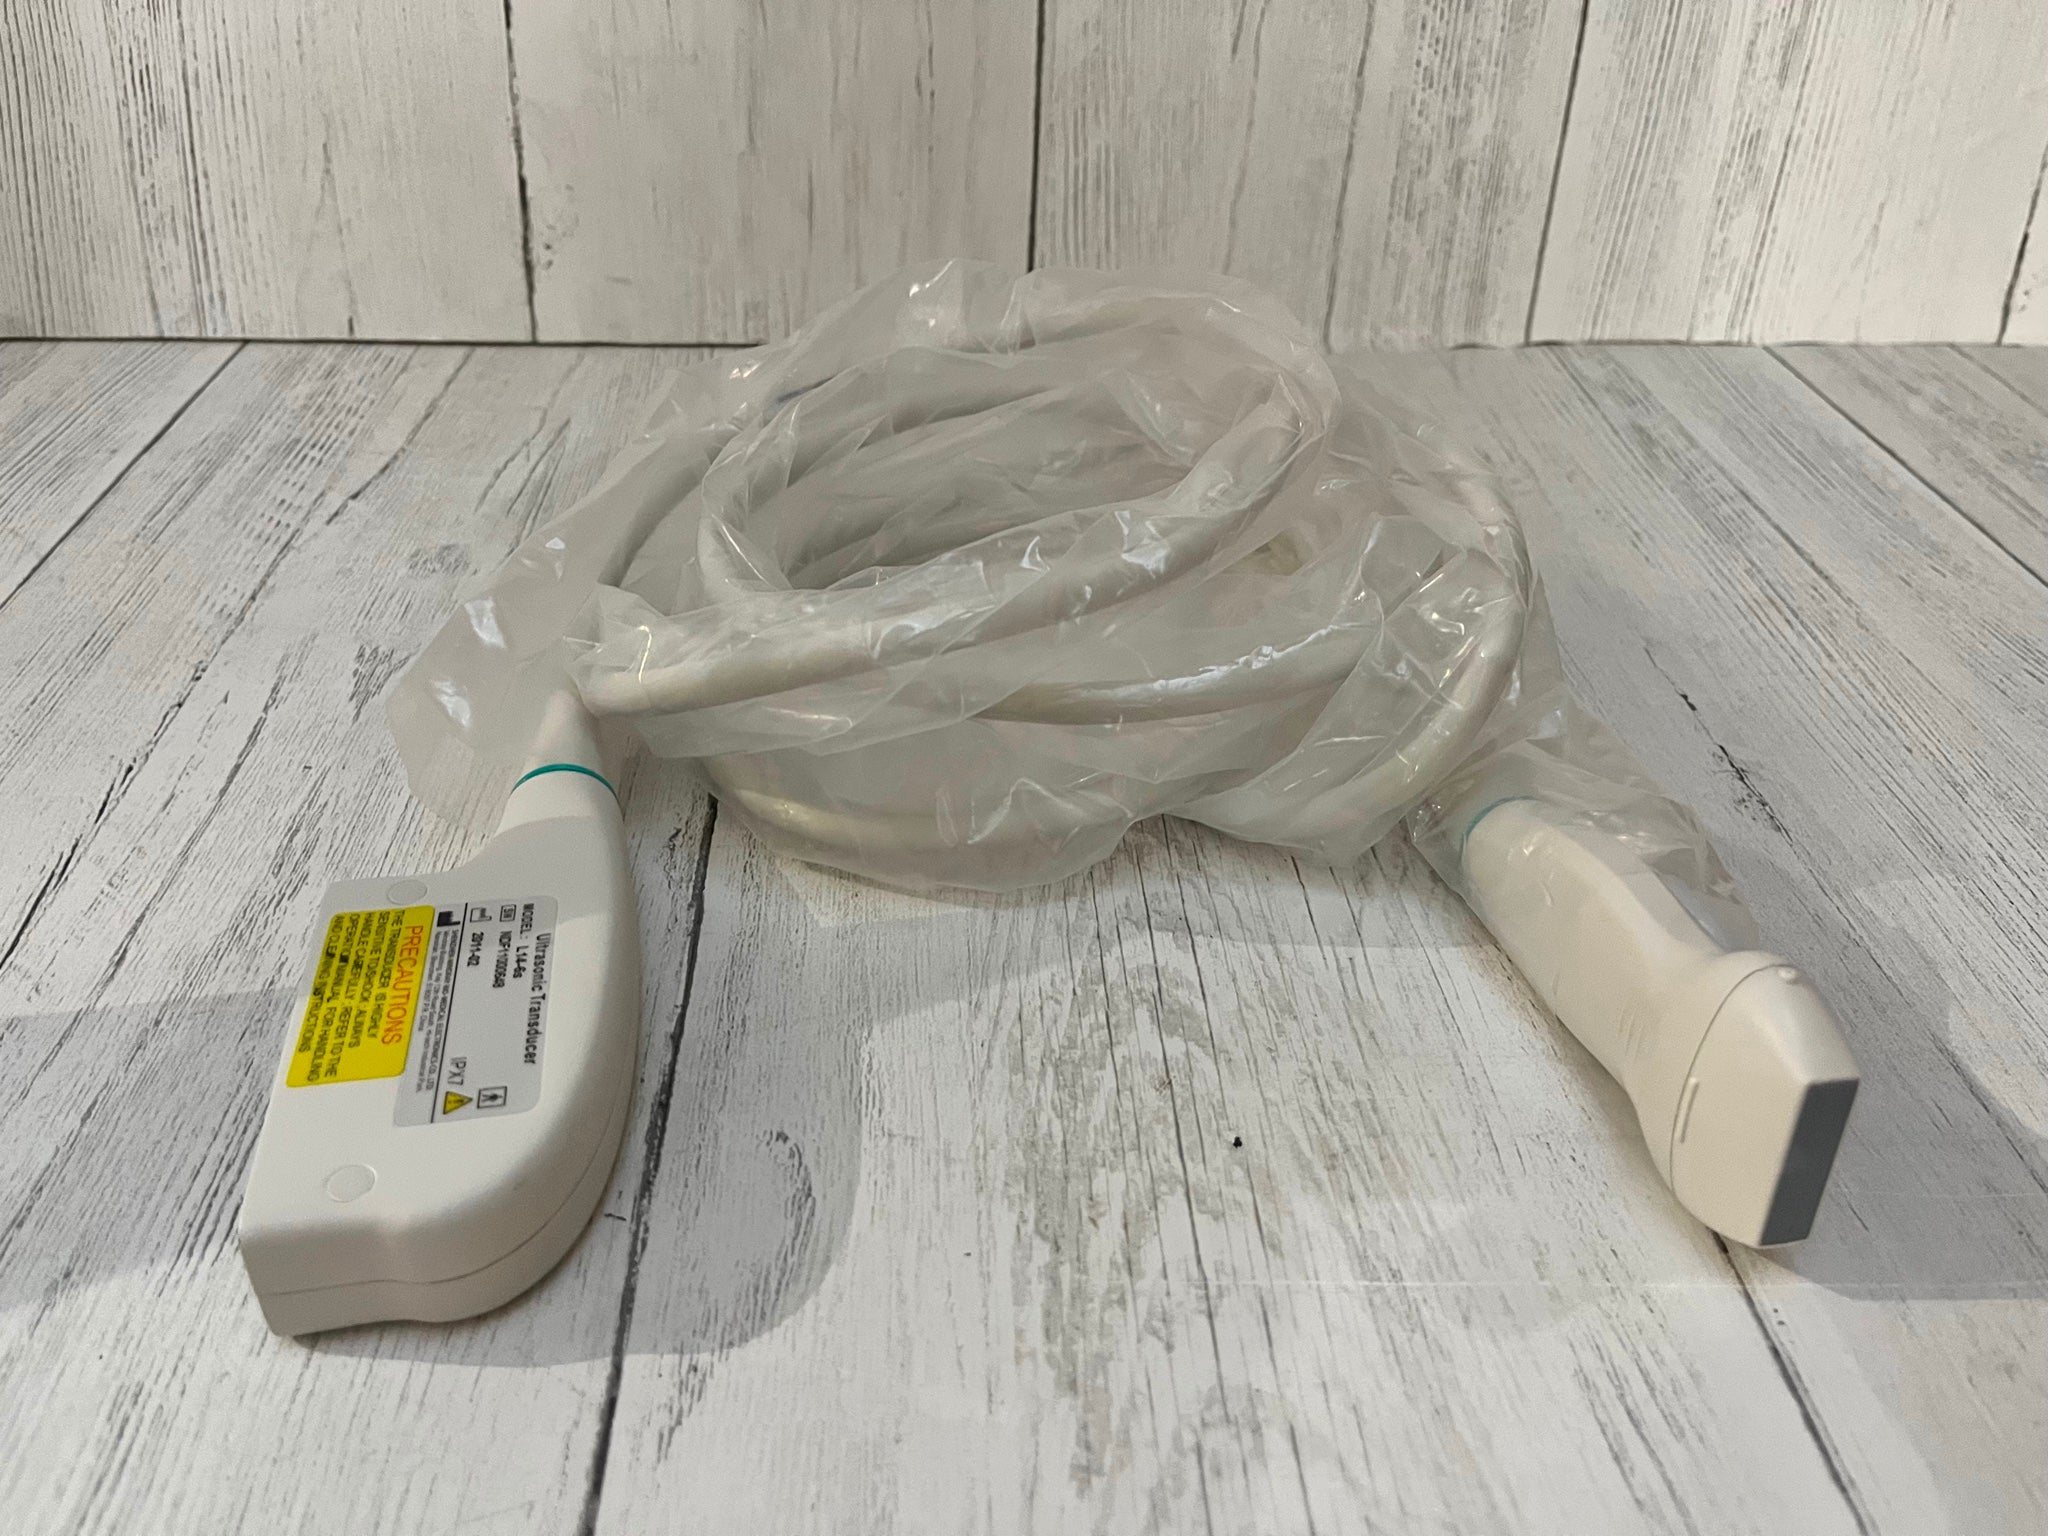

DIAGNOSTIC ULTRASOUND MACHINES FOR SALE

DIAGNOSTIC ULTRASOUND MACHINES FOR SALE

Philips iU22 - A Cart, 3D/4D Ultrasound

Sale price$ 21,585.66